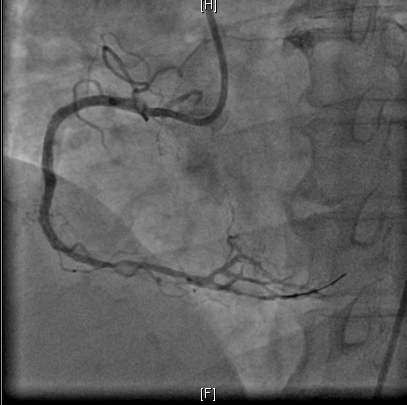

图1  RASER技术

图2 应用RASER技术治疗术前及术后的冠脉造影结果对比

准分子激光根据病变性质,选择合适的能量密度及脉冲频率,在这个病例中采用能量45mJ/mm²、频率40Hz共消蚀3次,球囊仍无法通过病变,随即换用旋磨导丝顺利通过病变并应用1.25mm磨头完成两次旋磨后,顺利完成球囊扩张及再次植入1枚支架,最终应用血管内超声(IVUS)精准评估手术后效果。